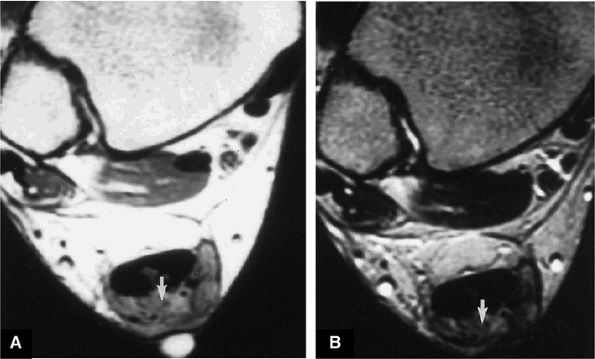

FIGURE 5.108 ● Insertional tendinitis with hyperintensity of the thickened distal Achilles tendon. Retrocalcaneal bursal inflammation and calcaneus marrow edema are shown. In contrast to non-insertional degenerative tendinosis, the process of insertional Achilles tendinitis demonstrates an inflammatory process histologically. Achilles enthesopathy is another term for insertional Achilles tendinitis. FS PD FSE (A) sagittal and (B) axial images.

|